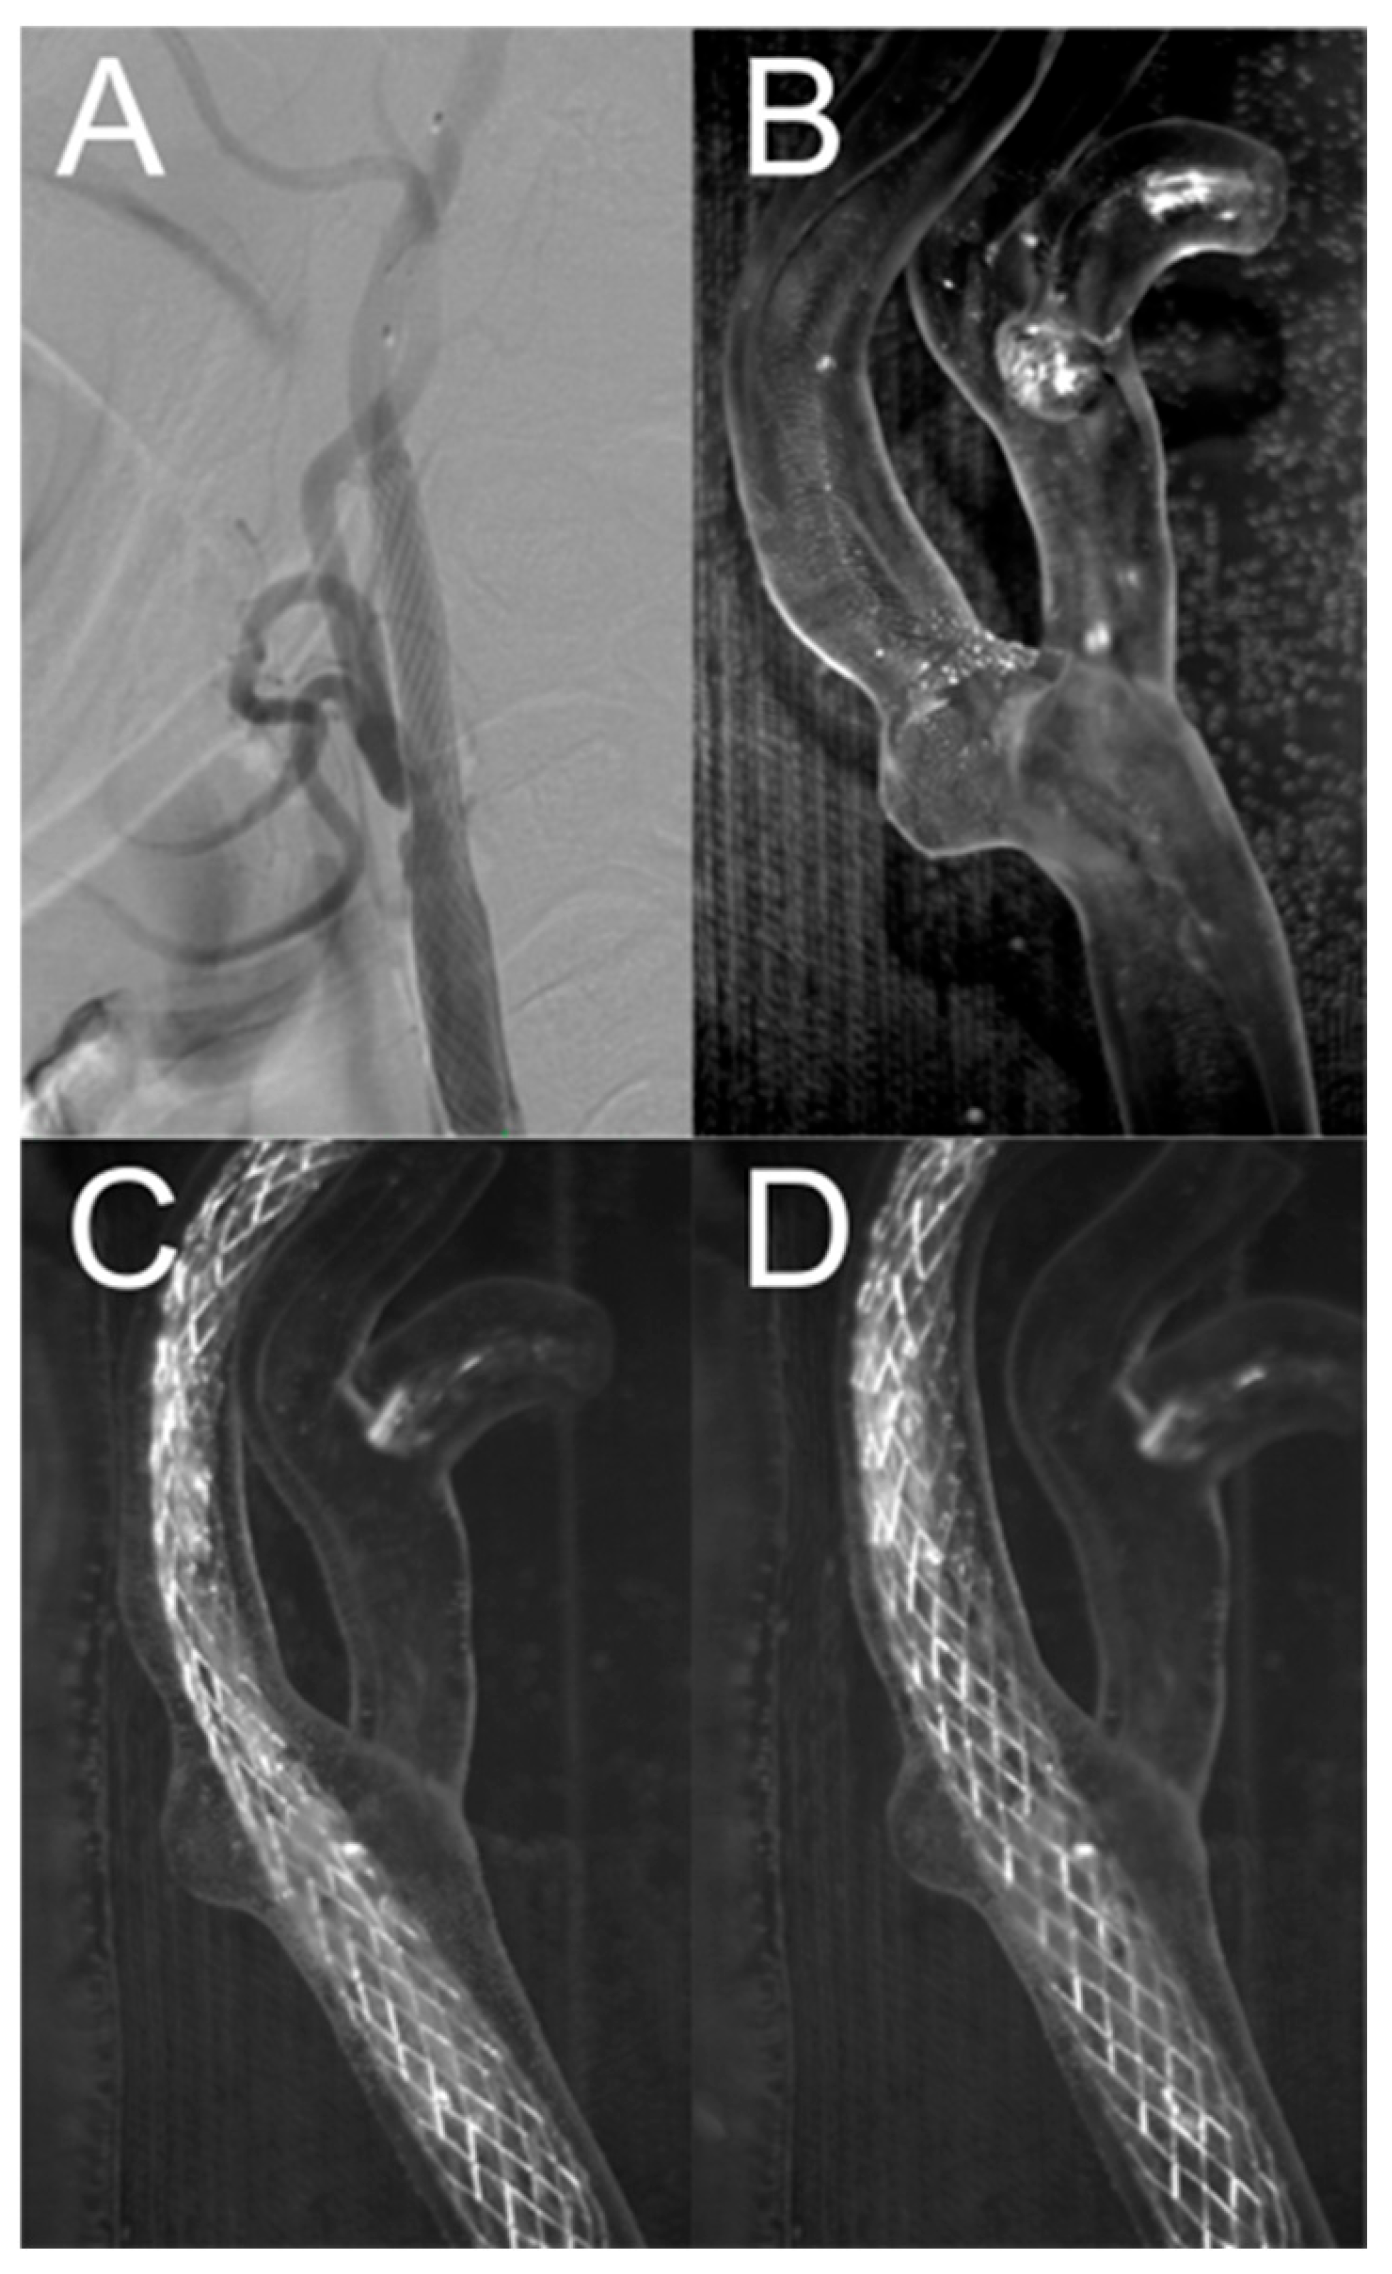

3.2. Percutaneous Carotid Artery Stenting on 3D-Printed Phantoms